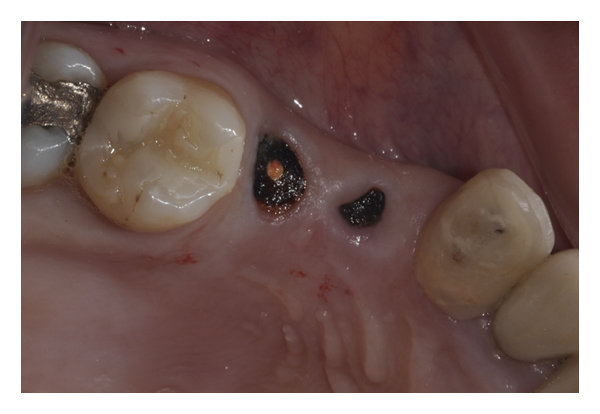

Best dentist near me | Are Retained Root Tips a Problem? Retained root tips occur when part of a tooth root remains after extraction, potentially leading to infection, pain, or even impacting nearby teeth and bone structure. If left untreated, retained root tips can cause complications, including cysts or abscesses. At Dr. Akkshaya Dental & Aesthetics, we offer thorough assessments and safe removal options to protect your oral health and prevent future issues.